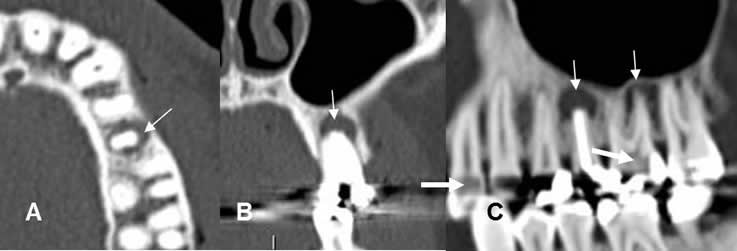

Fig 38. Enfermedad endodental.

A: TAC axial, B: TAC reconstrucción coronal y C: TAC reconstrucción sagital.

Reemplazo de la pulpa de los dientes, por caries extendidas internamente. (Flechas gruesas). Se encuentra perilucencia periapical, por enfermedad endodental.(Flechas delgadas).